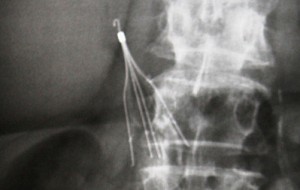

ivc filter retrieval x-ray

IVC Filter Retrieval: A Longer Dwell Time Means More Risk